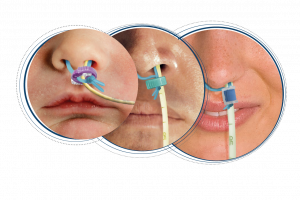

Forbedret håndtering og beskyttelse af både rene og brugte endoskoper.

Curas Endoskopbakker er en biologisk nedbrydelig og klinisk effektiv løsning, designet til at give hospitaler en mere sikker håndtering og samtidig reducere risikoen for luftbårne og overfladebårne kontamineringer.

Designet sikrer, at højdesinficeret endoskoper forbliver sikkert under transport og opbevaring før brug. Bakken kan også benyttes til brugte og kontaminerede endoskoper til umiddelbar iblødsætning og pre-desinfektion.